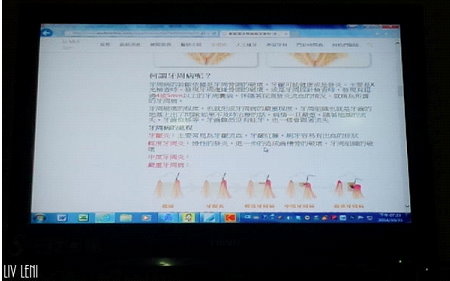

再來醫師準備了資料向我解說牙齦炎、牙周病的發展過程,

與各程度的治療應對,

透過實際的病理照片,幫助我對於牙周健康有透徹的認識。

並且再進一步的與專業資深牙助教導我,牙齦炎、牙周病的細部解說,

加上發問的解答時間,原本的觀念又更為完整啦~